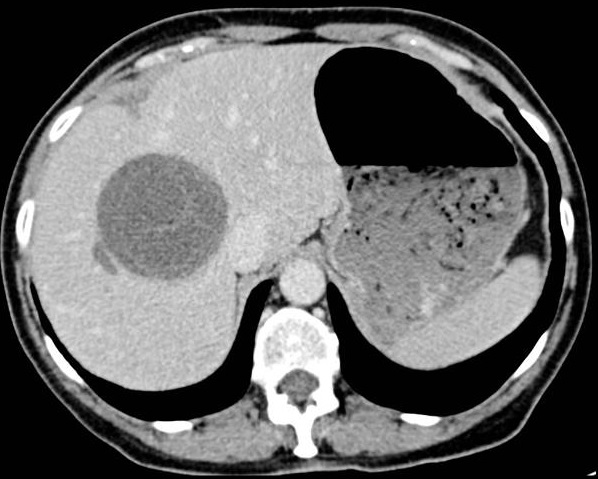

Aspect TDM d'une

kyte hydatique du foie . C'est un masse arrondie

hypodense a paroi un peut hyperdensite avec bord

lisse situe au foie droit . Image

TDM en coupe axiale a travers du foie

|

Une autre cas d'une kyte

hydatique du foie avec image d'un masse ovalaire

hypodense a paroi tres nette hyperdensite situe au

foie droit . Image des vesicules filles se retrouve

au sein de la lesion principale . Image radiologique

TDM en coupe coronal ( frontal ) |